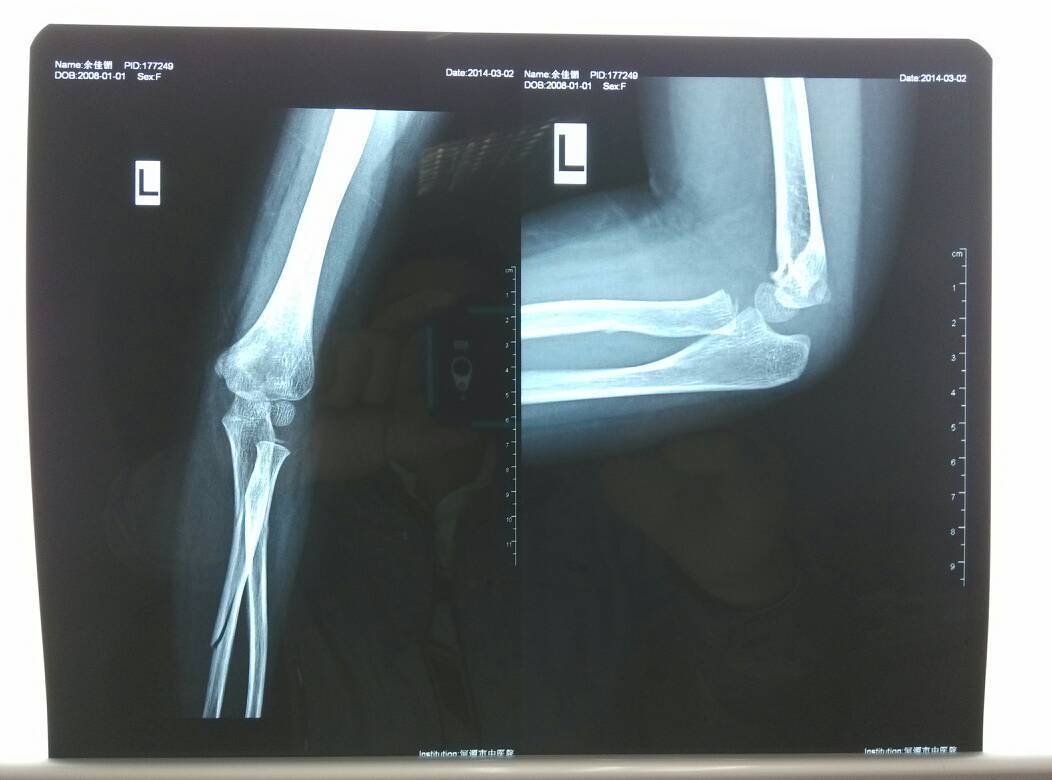

6岁小孩尺骨折夹板愈合要多久时间?期间要换药吗?不换药可以吗? 点击展开 匿名用户 2014-03-02 22:24 为您推荐: 其他回答 病情分析: 这种情况应该是桡骨的青枝骨折,如果没有皮肤的伤口不必换药的,小夹板过度可以很快愈合的。 指导意见: 建议首先观察局部肿胀消退的情况,一般肿胀消退后就不必特殊治疗了。一般一个月可以完全愈合。 匿名用户 2014-03-02 22:27 相关问题 6岁小孩左尺骨折夹板愈合要多长时间?中间要换药吗? 孩子友尺桡骨骨折带着夹板多长时间可以写字 三岁宝宝手扭了右尺跷骨青枝骨折夹板治疗需要吃什么药?